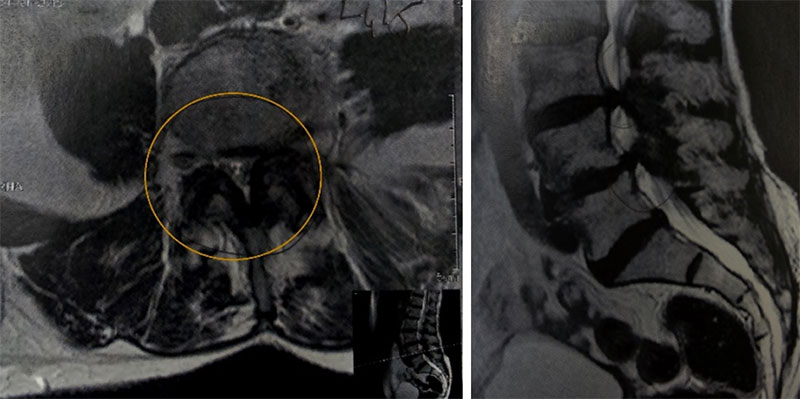

A ponderação T2 no corte sagital é útil para avaliação inicial do canal vertebral, sendo possível avaliar sobretudo compressões centrais pelo disco intervertebral degenerado e pelo ligamento amarelo hipertrófico. A ponderação T1 nos cortes sagitais é extremamente útil para avaliação de compressões na região foraminal, a perda do sinal da gordura ao redor da raiz no interior do forame, geralmente é sinal de compressão. Os cortes axiais são uteis em ambas ponderações, permitem avaliação do conteúdo do canal vertebral, estruturas neurais, local e lateralidade da compressão e estruturas que a causam. Também é possível avaliar a presença de derrame articular e cistos facetários.

Estenose do canal vertebral compressão no recesso lateral esquerdo.